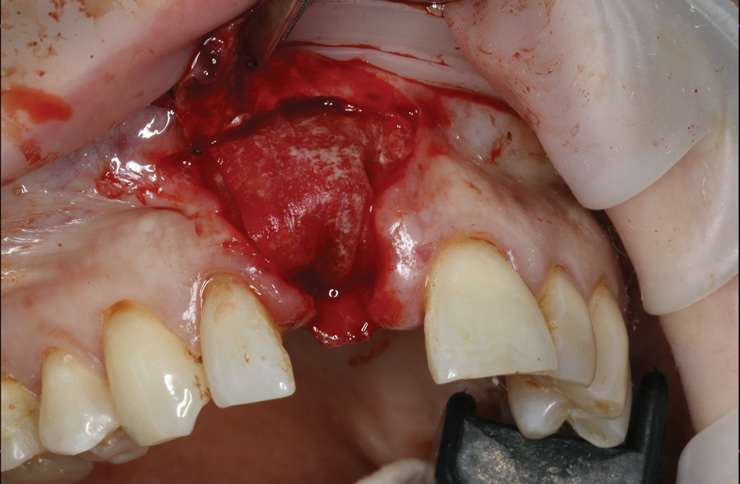

10. Tooth No. 8 with diagnosis of Grade III socket, requiring extraction followed by guided bone regeneration and a rotated pedicle flap to gain hard and soft tissue for future implant placement.

Figure 10

11. Tooth No. 8 with diagnosis of Grade III socket, requiring extraction followed by guided bone regeneration and a rotated pedicle flap to gain hard and soft tissue for future implant placement.

Figure 11

Based on the single extraction socket roadmap developed by El Chaar and colleagues, the socket of tooth No. 8 was diagnosed as Grade III and would require initial treatment that included the extraction of failing tooth No. 8 followed by simultaneous guided bone regeneration and soft-tissue augmentation by means of a rotated palatal pedicle flap (Figure 8 through Figure 11).27,28 The principles of and guidelines for both the ridge augmentation and rotated pedicle flap have been described in the literature and will not be focused on in this case report.27-30 The patient was temporized with a bonded Maryland bridge that was adjusted to avoid creating pressure on the tissue during healing (Figure 12).

Prior to the initiation of the surgery, the surgical guide was tried in to confirm proper seating and stability (Figure 15). A flapless approach was not considered because the need for further bone grafting at the time of implant placement had been anticipated through the digital planning. A slightly palatal crestal incision was made, followed by two vertical incisions on the mesial and distal aspects of the edentulous site in order to preserve the papilla and avoid additional esthetic compromise to the anterior sextant. Next, a full-thickness flap was elevated to facilitate removal of the tenting screw and permit visualization of the buccal plate (Figure 16). A standard guided protocol was followed to place the implant, and its final position mirrored that of the digital plan. As predicted, the prosthetically driven implant position resulted in an insufficient buccal plate (Figure 17); therefore, additional guided bone regeneration was performed to reinforce the area and prevent future breakdown (Figure 18 and Figure 19). Making periosteal incisions could have compromised the blood supply to the flap, so instead, it was stretched in order to achieve tension free coronal advancement.31The flap was secured utilizing horizontal mattress sutures with additional supportive interrupted sutures to ensure primary closure (Figure 20). An immediate postoperative periapical radiograph (Figure 21) and CBCT scan (Figure 22) were taken, demonstrating a final implant position centered with the planned location of the gingival zenith.